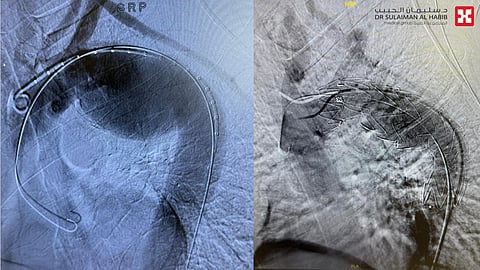

مشيراً بأنه تم إخضاعه إلى عملية القسطرة والتي استغرقت ساعة ونصف تحت التخدير النصفي، وتم فيها معالجة تمدد الشريان الاورطي وتركيب دعامة متطورة بنجاح، نقل بعدها إلى العناية المركزة (I.C.U)، وقد أبانت مؤشراته الحيوية في الساعات الأولى بعد القسطرة تحسن كبير، حُول بعدها إلى جناح التنويم.